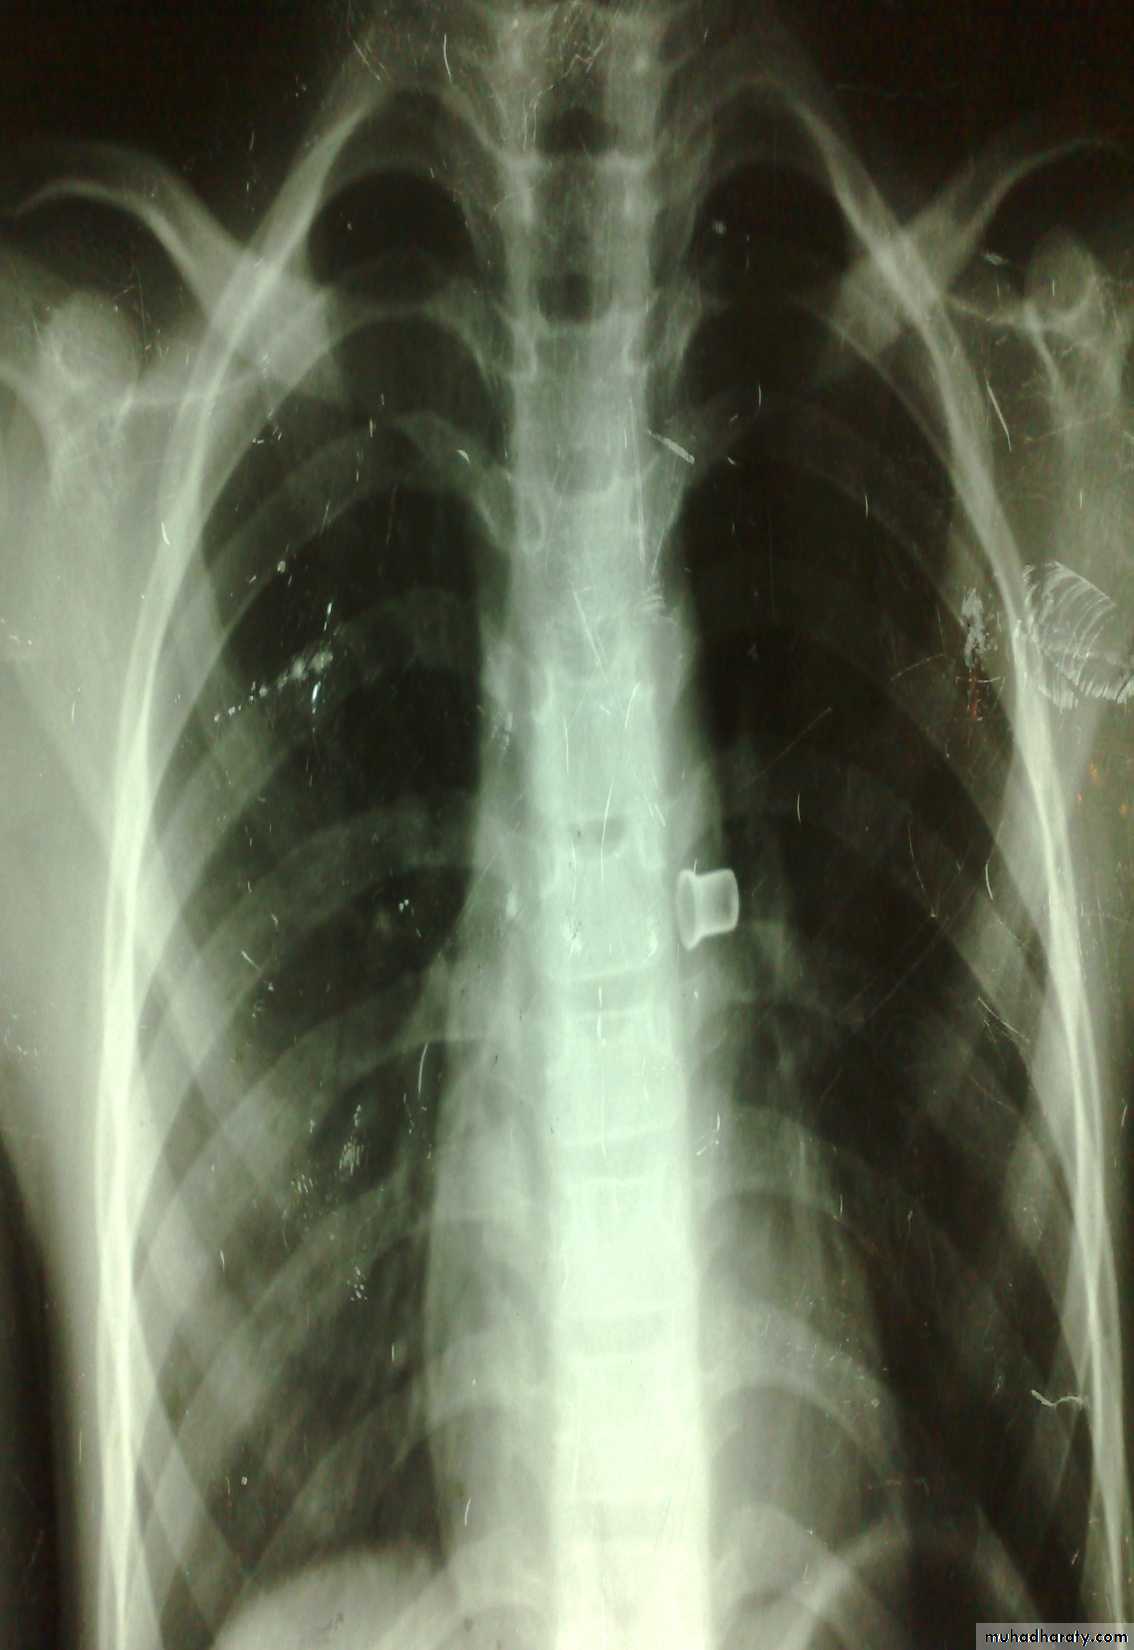

Hernia

VaricoceleDiagnosis: undescended testes

Problems:• Tumor

• Sterility

• Infection

• Orchitis (like appendicitis)

Treatment:

• If palpable do fixation

• If not palpable do laparoscopy

• If not present do nothing